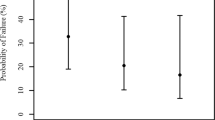

Logistic regression model was used to reveal the potential morphological risk factors for secondary glaucoma, including covariates of AOD500, TIA, ACD, CCT, high insertion of iris, peripheral anterior synechia, and IOL implantation in sulcus (Table 4). In univariate analysis high insertion of iris, peripheral anterior synechia, and IOL implantation in sulcus were significantly associated with higher incidence of secondary glaucoma. Multivariate analysis identified high insertion of iris (OR 3.40, 95% CI 1.03–11.17, p = 0.03) and IOL implantation in sulcus (OR 1.39, 95% CI 1.07–4.85, p = 0.04) as independent risk factors for secondary glaucoma.